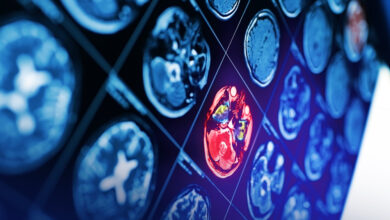

الطب النووي

الطب النووي استخدامات تشخيصية وعلاجية الطب النووي هو المجال العلمي الذي يوفر تنفيذ التطبيقات العلاجية من خلال الأجهزة المسماة كاميرا…

السكتة الدماغية

السكتة الدماغية إعادة التأهيل هي السبيل الأول لعلاج الآثار عبر تنمية قدرات الجسم على مريض السكتة الدماغية أن يدرك أن…